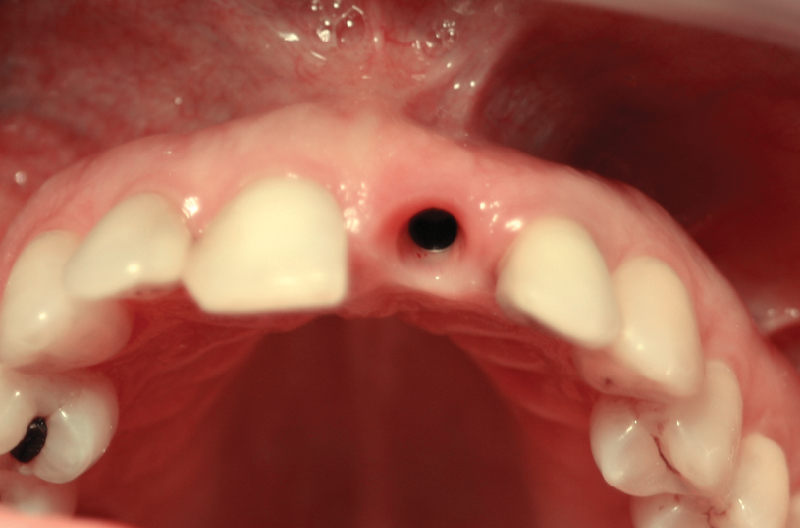

FIG. 5 – A 4 mesi dall’intervento dopo aver rimosso la corona provvisoria e il tappo di guarigione: il tessuto gengivale si presenta sano e ben conservato

FIG. 6 – Moncone MultiTech ibrido titanio/zirconia

FIG. 7 – Prova del moncone MultiTech ibrido; la spalla a filo gengiva permetterà una perfetta pulizia del cemento in eccesso

FIGG. 8, 9 – Visione della corona in ceramica in situ